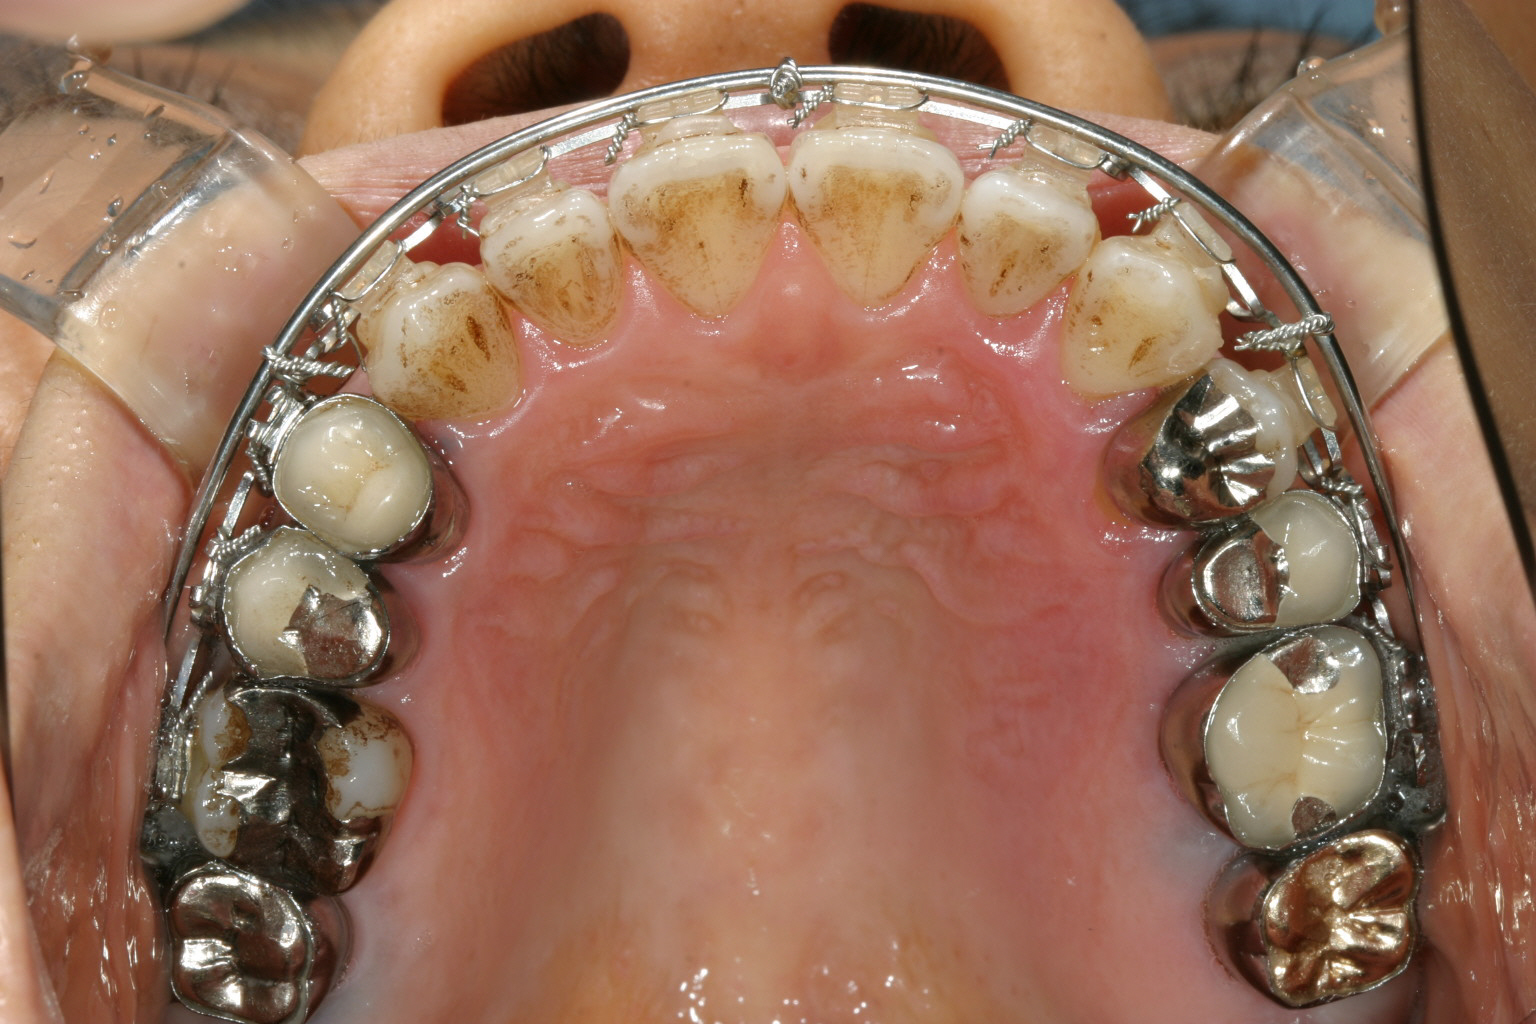

マルチループワイヤーと外側にマリガンワイヤー使用して1年後です。 もう殆ど歯列は改善してます。

下顎マルチループワイヤー、上顎にマルチループワイヤーとマリガンワイヤー使用で殆ど上下切端の隙間も閉じてきました。

上顎も綺麗な歯列に改善しました。